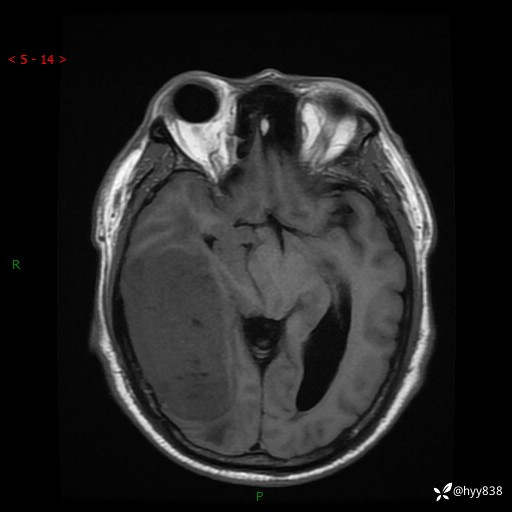

患者性别:男

患者年龄:56岁

简要病史:外院CT提示脑膜瘤,为进一步诊治来我院

临床诊断:颅脑占位

颅脑MRI平扫+增强